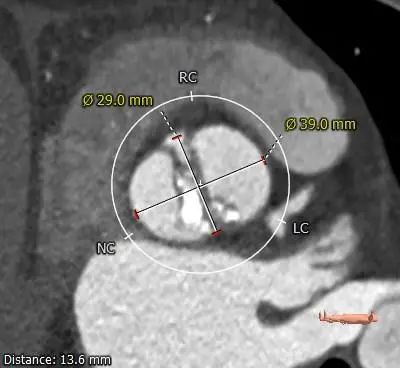

SOV DIAMETER

LVOT